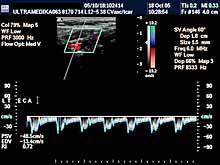

A) Krvni sudovi vrata

Vrsta i sadržaj pregleda:

- Pregled velikih krvnih sudova vrata CD i CPA

modom (obavezno karotidnih i vertebralnih arterija celim tokom).

Pregled podrazumeva procenu ukupne debljine krvnih sudova (indirektna

procena koronarne bolesti), procenu stepena suženja, karakteristika aterosklerotičnog plaka, procena hemodinamike i postavljanje

indikacija za operativno lečenje.

Primenjena tehnika:

- Sono CT,

- XRes,

- 2D Broad band,

- Broad band - CD,

- CPA ,

- CPD.

Preporučeni pregledi:

- nakon 45. godine starosti,

- obavezno ako postoje

faktori rizika

(hipertenzija, pušenje, stres, poremećaj nivoa masti u

krvi, kod sumnje da postoji koronarna bolest),

- kontrola na 6-12

meseci.